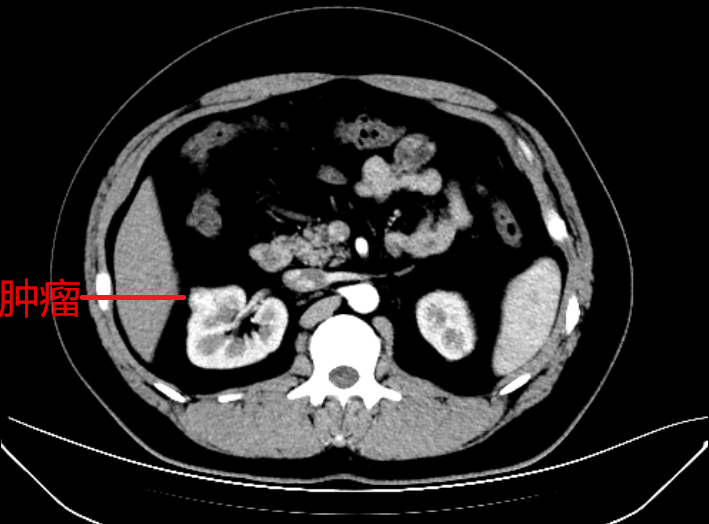

30岁的刘先生体重110kgBMI指数34.7,因过度肥胖,每年定期体检而意想不到的是这次体检时发现右肾有个肿瘤,但自觉无任何症状。为求确诊,在家人的陪伴下慕名来到捷克论坛 泌尿四科就诊。

经杨科主任团队诊治后,诊断为右肾占位性病变。在全麻下行腹腔镜下右肾部分切除术,术中完整切除2cm左右肿物。刚刚经历了一场拆弹手术的刘先生现正处于康复期。